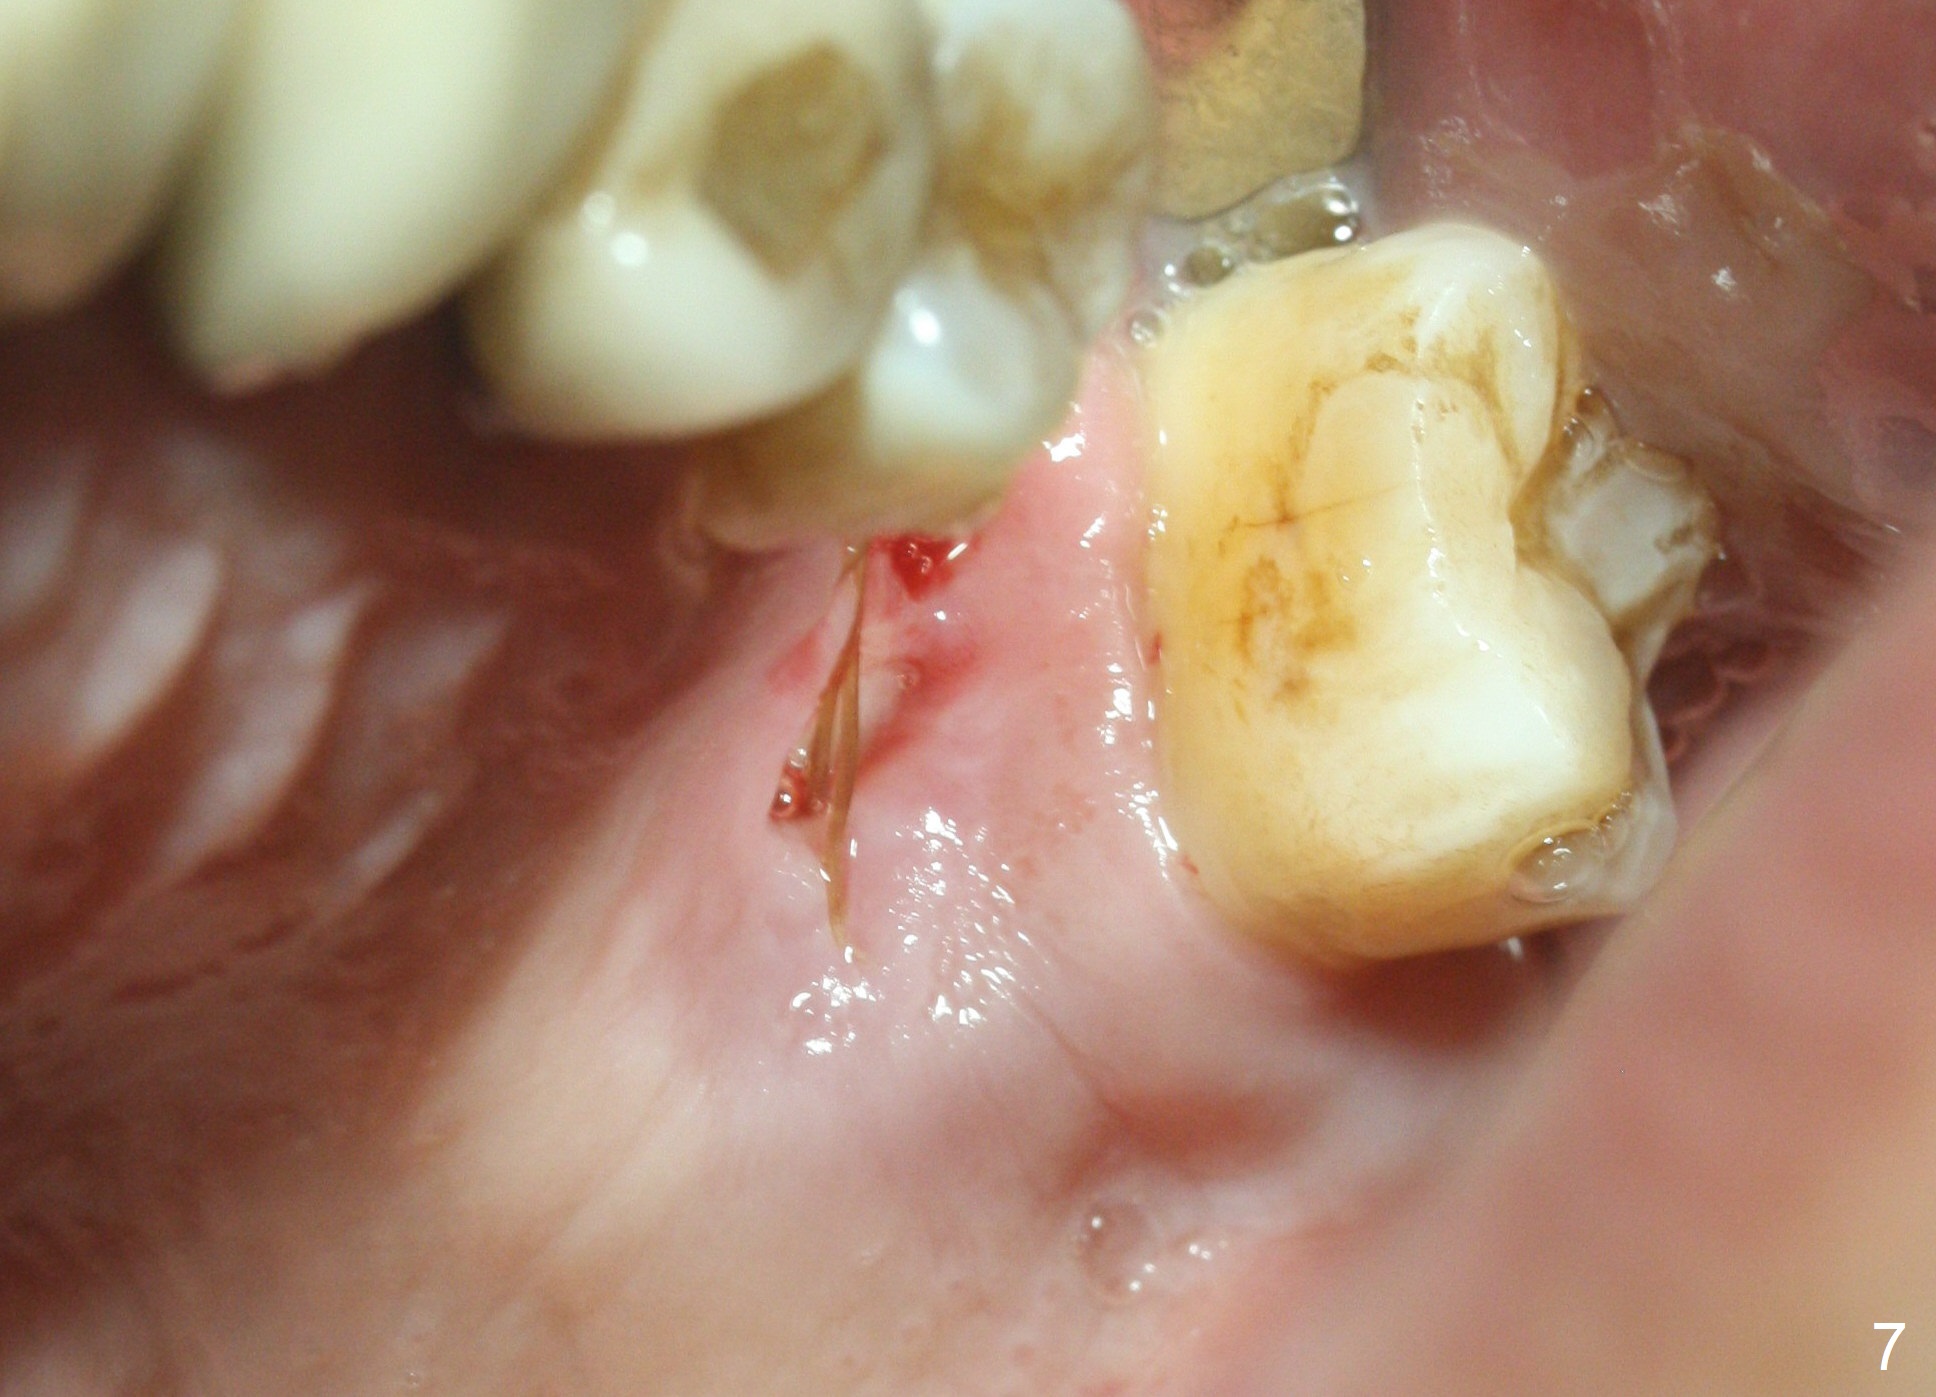

When the tooth #14 is extracted, the buccal plate is lost, while the apex of the palatal socket is perforated.  The palatal slope of the septum appears to be a suitable site for osteotomy, but the depth seems to be 2 mm.  After sequential osteotomy until 5.3 mm with drills, a 5.9 mm SM tap obtains stability (Fig.2).  A 5.9x8 mmm implant is placed with barely sufficient stability after 1 piece of PRF membrane and VeraGraft (Fig.2-4).  The implant rotates and dislodges when an abutment is being placed.  Neither do 6-8x17 mm Tatum taps achieve primary stability.  Socket preservation is performed, followed by periodontal dressing (Fig.5).  Primary stability might have been obtained if a smaller IBS implant with fins were placed in the palatal socket.  The periodontal dressing has dislodged 1 week postop; the socket appears healing (Fig.6,7).  Bone graft seems to be minimal or bone density of the graft is low (Fig.8).  The socket heals with a wide ridge 2 months post socket preservation, but the tooth #15 seems to be buccal (Fig.9) and mesial (Fig.10) shift.  After use of Magic Split and Expanders (until 3.8 mm for 13 mm), try 5 mm dummy implant (Fig.11).  If 6 mm one fails to achieve stability substantially, switch to 7 mm Tatum tapered tap provided there is enough mesiodistal space (use 8 mm implant positioner to gauze the space beforehand (preop)).  Consider using Vanilla (not Vera) Graft to fill in the gap between implant and osteotomy.  When primary stability is obtained, place a nonfunctional provisional to prevent further shifting (Fig.11 white outline).  After osteointegration, use the provisional (reline and separator) to distalize the tooth #15.